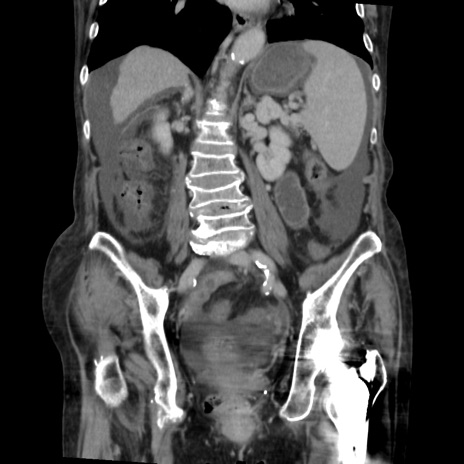

症例31(冠状断像)

【症例】80歳代 女性

【主訴】腹部膨満感

【現病歴】他院にて肝硬変にてフォロー中。1週間前から便秘、腹部膨満感、臍部腫瘤あり受診となる。

【既往歴】肝硬変

【身体所見】腹部膨隆あり、皮膚変化なし、疼痛なし。

【データ】WBC 4600、CRP 0.25